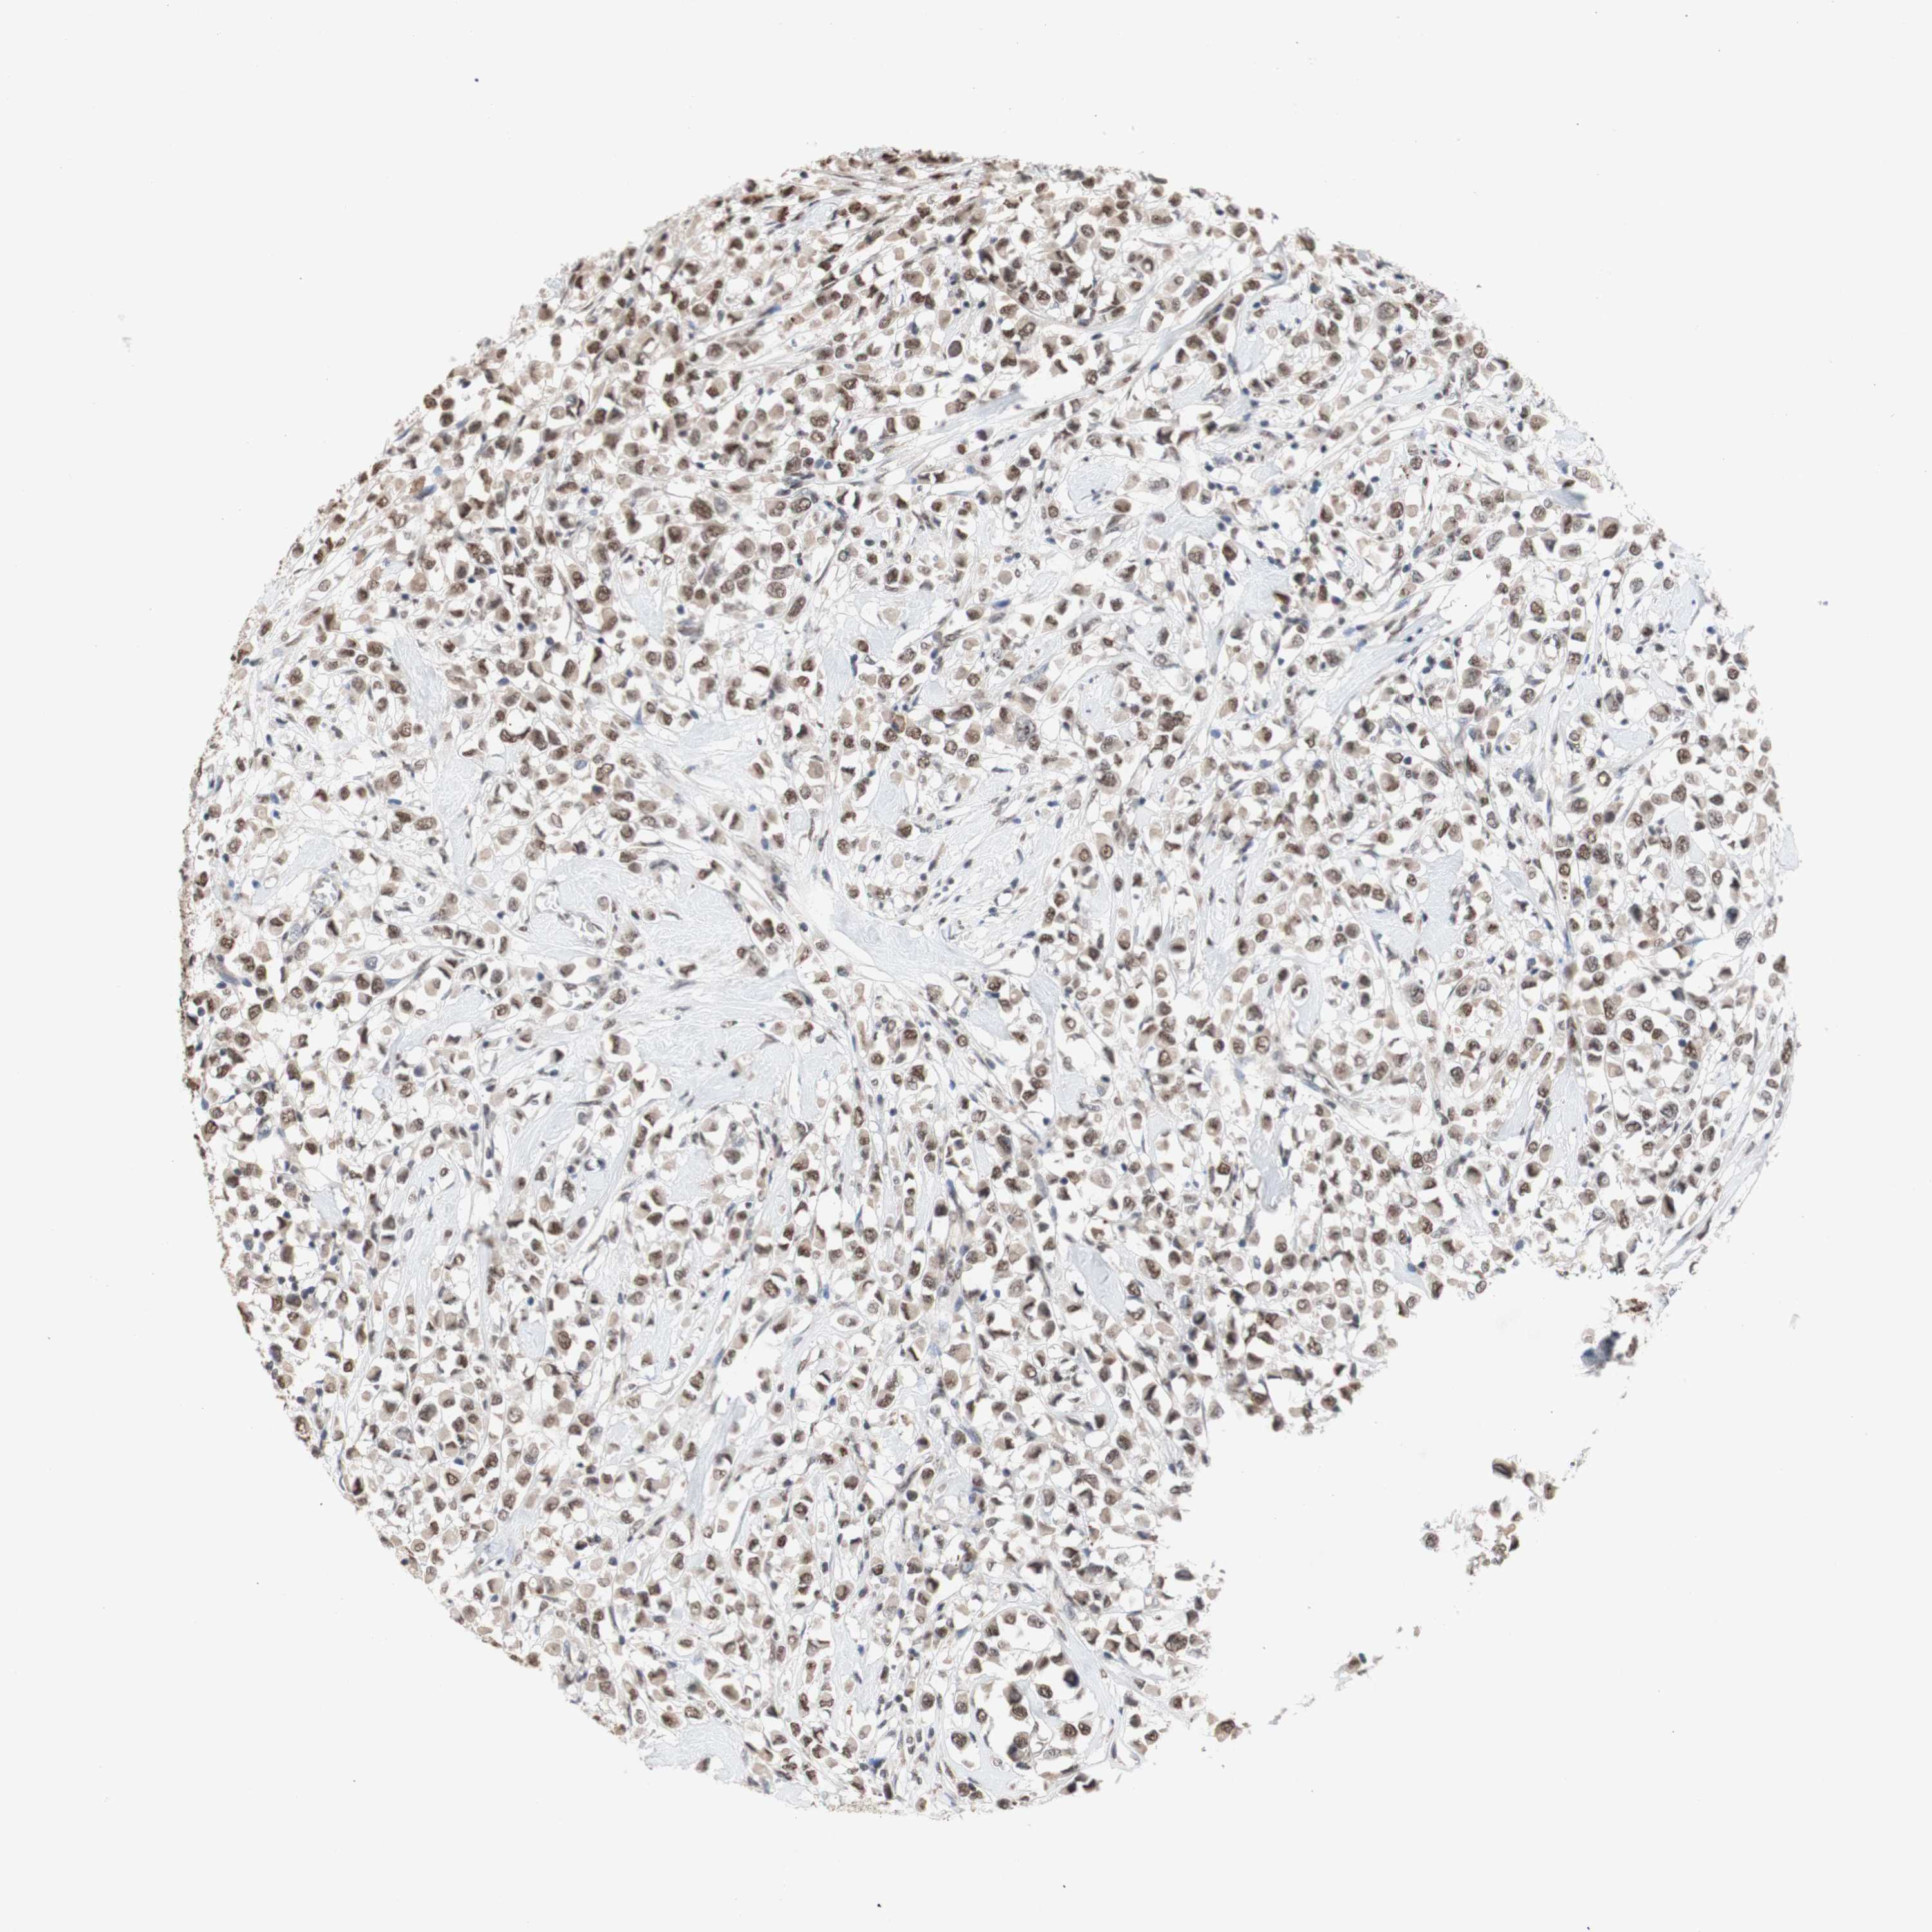

BRCA TCGA BRCA VALIDATION PROTEIN EXPRESSION

ANTIBODIES

AND

VALIDATION